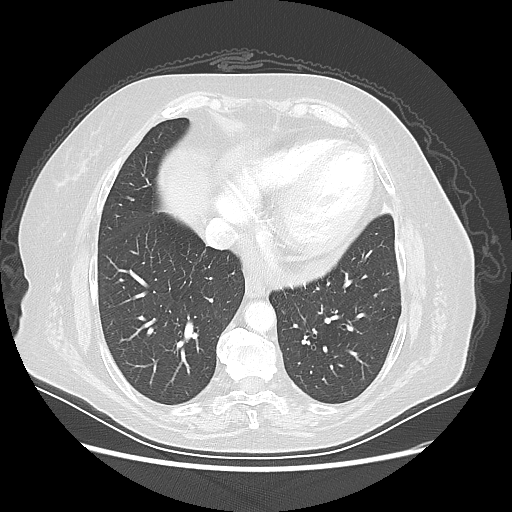

Original NATIVE CT scan (input)

Full window (WL 1023.5, WW 4095 β†’ Low βˆ’1024, High +3071)

Lung window (WL -600, WW 1500 β†’ Low βˆ’1350, High +150)

Mediastinum window (WL 40, WW 400 β†’ Low βˆ’160, High +240)